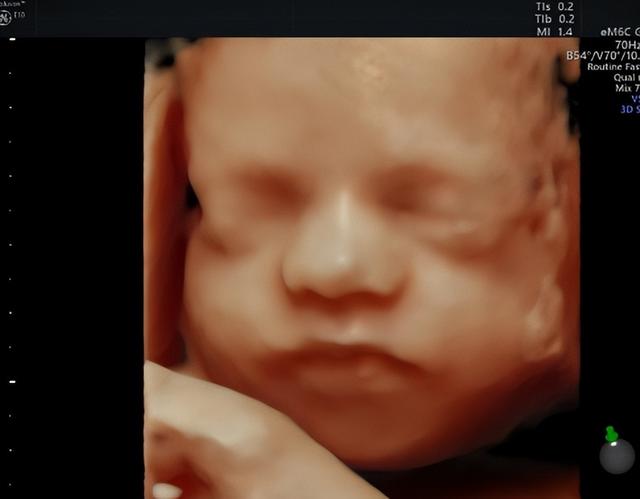

四维彩超还有一个名字“宝宝的0岁写真”。相比三维彩超,四维彩超更形象、更立体、更动态。

筛查胎儿畸形,检查宝宝在子宫内的发育情况,是否符合孕周,四肢、颜面部、内脏有无畸形,以及羊水、脐带情况。因此,在合适的时候做四维彩超是非常有必要的。

从医学角度来说,做四维检查可以全面、多维度的观察胎儿的发育情况,能够检查胎儿的面部、脊柱、神经系统、泌尿系统、消化系统、心脏是否健康。

医生通过细致的观察,为早期诊断胎儿先天性畸形和先天性心脏疾病提供准确的科学依据。

湖南妇女儿童医院引进多台美国GE系列机器,满足从早孕期到孕晚期的全程早期检查和诊断,在四维检查中成像高清、立体,大大提升了临床检查和诊疗的准确度。